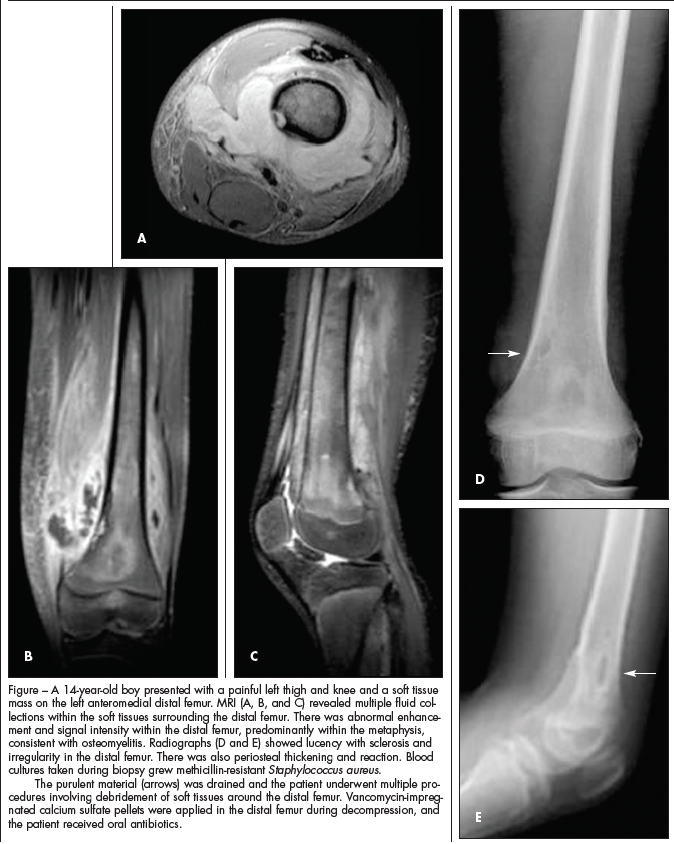

When community-acquired MRSA is suspected (Figure), the first-line options include clindamycin(, the addition of an aminoglycoside and, rarely, vancomycin(.6 Vancomycin is the first-line agent for MRSA infection secondary to nosocomial infection. Clindamycin may be given as the first-line drug for community-acquired MRSA, particularly in patients who are allergic to or intolerant of b-lactam antibiotics. Although a number of the newer antibiotics (eg, lin-ezolid and quinupristin/dalfopristin) have been shown to be effective against MRSA, these agents should be used only with the advice of an infection specialist.